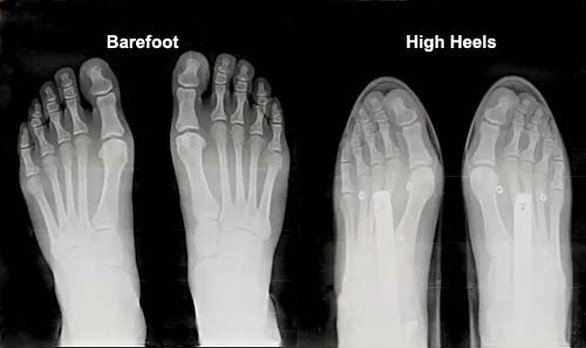

They also cause deformity of the toes. Heels, espicially pointed toe heels force the toes into an unatural shape. Club foot.

When women wear flats with normal rounded front, they have better shaped feet.

Heels are also terrible for the spine.